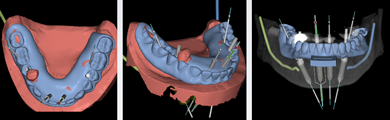

The workflow for planning full-arch reconstructions with dynamic navigation includes the following:

• Planning implant position

• Planning bone reduction

• Planning position of fixation screws

• Selecting anatomic registration points

Planning Implant Position

The position of the implants must be prosthetically driven. Any of the major software planning tools can be used with dynamic navi- gation. The software included with the navigation system allows for dual scan planning, as dual scan images are suitable for this prosthetically driven approach. Once the plan is completed, the data should be sent for fabrication of the provisionals. If navigation software is used for implant planning, the data can be exported as individual or linked generic .stl files, or if planning is done without the navigation software, the data can be imported into the navigation system.

Planning Bone Reduction

For implant planning, bone reduction should be done using small preps-1-mm rods placed just above the level of the platforms (Figure 19). During surgery, the entry points of the preps are used to mark the reduction height using navigation. A navigated straight or 45º handpiece is then used to connect the points and complete the osteotomy, using navigation to ensure that the lingual or palatal soft tissue is not perforated.

Fig 28. Views of virtual digital denture used to plan implant position.

Figure 28

Fig 29. PMMA-milled transitional provisionals. Arrows indicate occlusal locks.

Figure 29